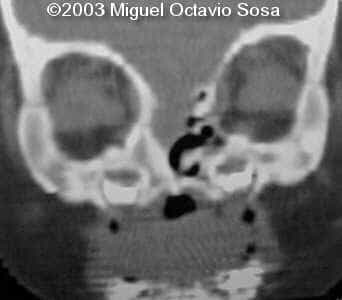

19-year-old primigravida. During third week of pregnancy, she is vaccinated with anti-measles vaccine, without knowing about the pregnancy. There are no important details before the pregnancy. These are images of the face of the fetus. Pay specific attention to the midface.

19-year-old primigravida. During third week of pregnancy, she is vaccinated with anti-measles vaccine, without knowing about the pregnancy. There are no important details before the pregnancy. At 22nd week, an ultrasound is performed demonstrating a single nasal channel on the left side and absence of right nostril.

A female newborn was delivered at 38 week, by cesarean section due to breech presentation. Size of right eye is bigger than left, and there is total absence of the right nostril. Apgar 9 at birth. No complications during postpartum. Newborn is actually under study by plastic surgeon.

These are the 3D CT reconstruction.